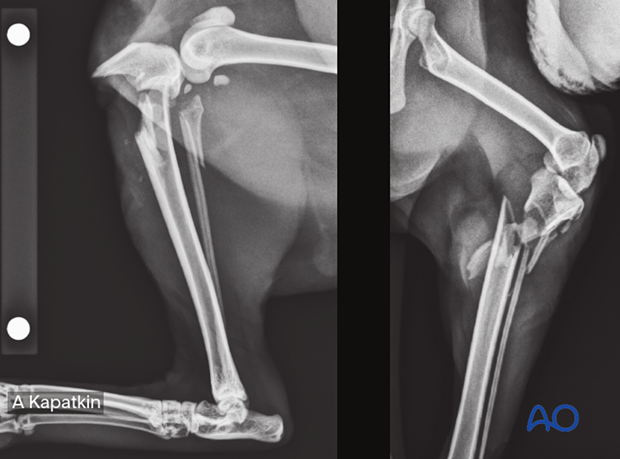

To help identify the fractures, x-rays of most fracture types have been included in the diagnosis section.

The cat proximal tibia material includes a detailed description of the following fracture types and fixation methods.